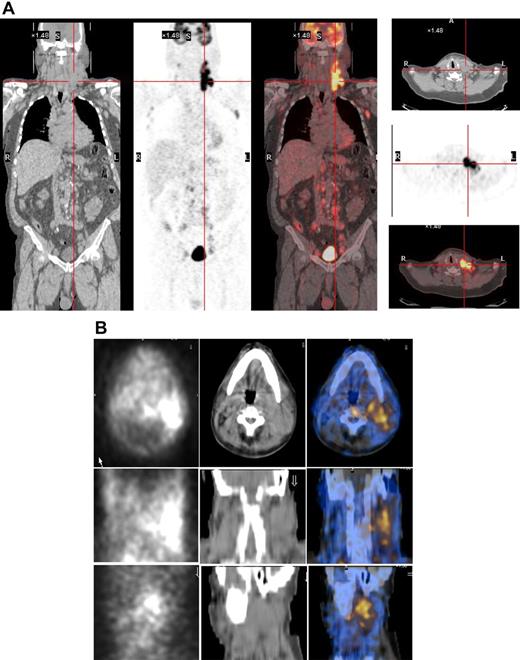

Both HL patients also showed favorable lesion/bone marrow dosimetry estimates after receiving diagnostic 131I-L19SIP, with an absorbed dose of radioactivity to the target lesions—a pulmonary lymphoma lesion (patient HL1) and a left basal pulmonary lesion and a right axillar lymphoma conglomerate (patient HL2)—estimated to be approximately 14 and 22.7 Gy, respectively. The absorbed dose to the red bone marrow was calculated to be 1.3 and 0.85 Gy for HL patients HL1 and HL2, respectively. In HL patient HL1, the SPECT-CT images acquired 12 days after a dose of 5.55 GBq 131I-L19SIP demonstrated selective ED-B FN targeting in multiple parenchymal lung lesions and in enlarged supraclavicular and lumboaortic lymph nodes with all such sites corresponding to high 18F-FDG uptake on baseline PET-CT scans (Figure 6). In the second HL patient (HL2), the SPECT-CT images acquired 12 days after a dose of 3.7 GBq 131I-L19SIP demonstrated selective ED-B FN targeting in multiple enlarged axillar and supraclavicular (both sides), paratracheal, subcarinal, pleural, as well as peritoneal and iliacal (both sides) lymph nodes. ED-B FN–expressing lymphoma lesions were also found in the right and left basal lobes of the lung. All ED-B FN–expressing lymphoma lesions corresponded to high 18F-FDG uptake on baseline PET-CT scans (Figure 7). Both HL patients experienced a partial clinical response according to RESCIST criteria at 1 month after therapy with shrinkage of the sum of diameters of the measurable lymphoma lesions of 44% (134 to 75 mm; baseline to 1 month after treatment) and 39% (417 to 256 mm) for patients HL1 and HL2, respectively. This partial response was confirmed at 2 and 3 months after 131I-L19SIP therapy for both HL patients. The 3 lymphoma patients did not experience any acute toxicity during or after 131I-L19SIP therapy. Mild and transient thrombocytopenia was observed in both HL patients, but not in the SLL NHL patient, with a nadir of 22 and 52 × 109 platelets/L for patients HL1 and HL2, respectively, at 6 weeks after 131I-L19SIP injection.

18F-FDG PET scans and 131I-L19SIP SPECT-CT images from an advanced Hodgkin lymphoma patient (HL1).18F-FDG PET scans show intense glucose metabolism in multiple enlarged mediastinal lymph nodes, intrapulmonary lesions (leftmost column, first 4 images; intrapulmonary lesion marked), as well as in lumboaortic lymph nodes (leftmost image in lowest row). The same patient received intravenous injections of 185 MBq and, subsequently, 5.55 GBq 131I-L19-SIP. SPECT-CT coronal (top right panel) and transaxial images of the thorax (rows 2-4) as well as the upper abdomen (lowest row) are shown, demonstrating selective uptake of 131I-L19SIP into the 18F-FDG–labeled lymphomatous lesions.